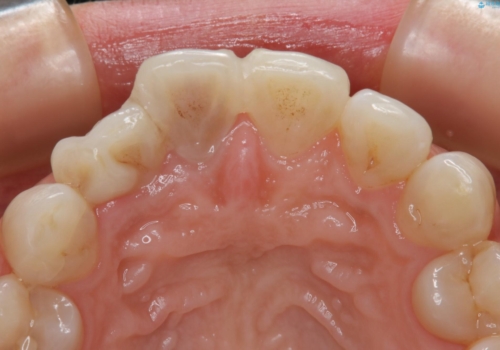

- 1週間ほど前に自転車で転倒して前歯をぶつけた後、歯の色が変わっていることが気になり受診された方です。診察の結果、失活及びエナメル質に多数の亀裂が認められたため、根管処置およびセラミッククラウンによる治療を行いました。元々右上2番目の歯の形が気になっていたとの事で、左右対称の形に近づけるように補綴しました。

左上1番目の歯は失活していませんでしたが、歯の表面に多数の亀裂が認められました。患者様のご希望により、前歯3本をまとめて補綴処置することとなりました。土台となる歯質の色が異なる状態でしたが、熟練した技工士さんの技術により3本とも同じ色味になるように仕上げていただきました。色味、形態ともに自然な被せ物に大変喜んでいただけました。